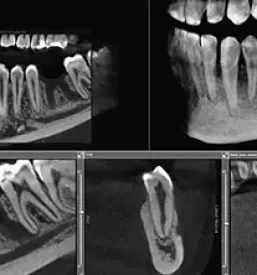

Imamo sodobno opremljeno zobozdravstveno ordinacijo, v kateri vam hitro, ugodno, predvsem pa kvalitetno nudimo peskanje zob. K nam v Ljubljano pa se naročite tudi, če potrebujete: